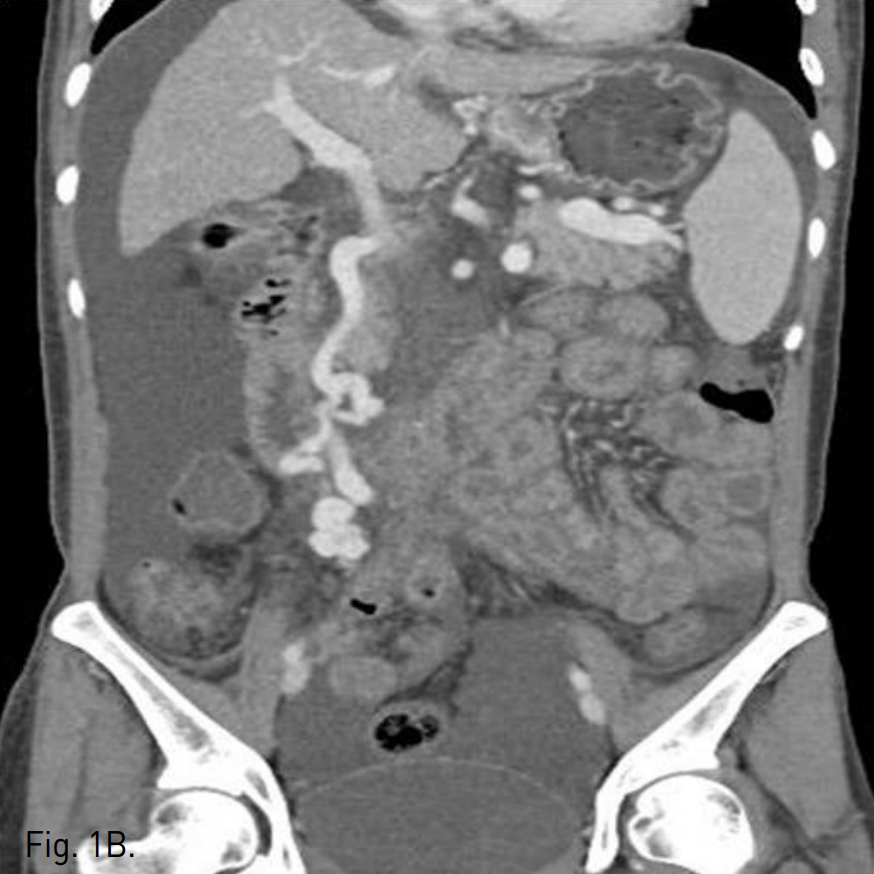

복부 CT에서 정맥류로 생각되는 확장되고 구불구불한 모양의 이상 혈관구조가 주문맥 윈위부에서 기시하여 우하복부 장간막을 따라 있으며, 일부 혈관구조가 소장 벽에 노출되어 있는 모습을 보인다. 그 외에 위, 식도에도 정맥류가 관찰되고 복수와 간 표면의 불규칙화, 경한 비장종대, 소장의 점막하부종이 동반되어 있다(Fig. 1A, B).

Fig. 1

A. Contrast-enhanced abdominal CT shows a tortuous and dilated vasculature (arrow) suggesting varix is located in mesentery of right lower quadrant area and some branching vessels from varix are protruding into adjacent intestinal wall (arrowheads).

B. Coronal scans show entire course of the varix supplied from main portal vein.